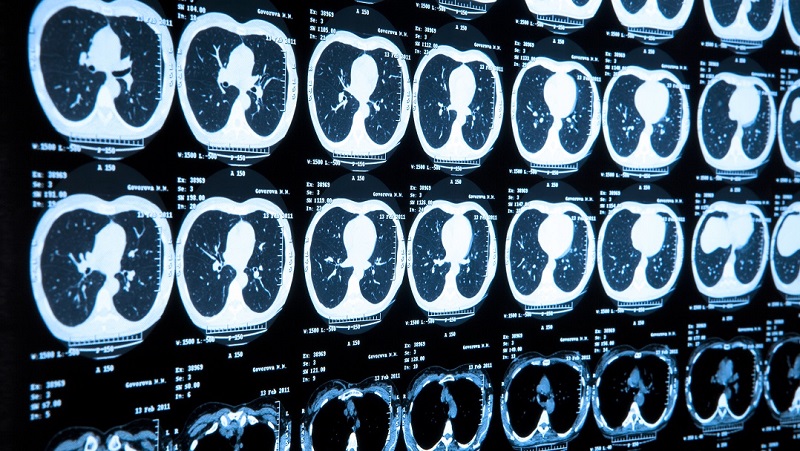

Kanser teşhisi için çeşitli görüntüleme yöntemleri vardır. Ultrason, tomografi, MR ve PET bunların en önemlileridir. Sadece bir kitle görmek bunun kanser olduğunu göstermez. O nedenle mutlaka parça alınarak (biyopsi) mikroskop altında incelenmesi ve patoloji raporu haline dönüşmesi gereklidir. Halk arasında biyopsi alınırsa yayılır şeklinde yanlış bir görüş vardır. Biyopsi kanserin yayılmasına sebep olmaz, kanser zaten yaygınsa alınan biyopsi sonrası yayılmış gibi bir yanlış düşünce oluşabilir. Bu doğru değildir. Biyopsi tanısı olmadan kanser tedavisi yapılmaz.